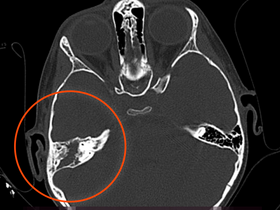

- Компьютерная томография с тонкими срезами височной кости без контраста – наиболее часто используемый метод диагностики. Визуализация помогает спланировать хирургическое вмешательство и предоставляет отоларингологу значительное количество полезной информации.

Холестеатома – это доброкачественное новообразование (киста) уха, но для установления точного диагноза может потребоваться консультация онколога. Холестеатома имеет определенные КТ признаки, которые отличают ее от раковой опухоли.